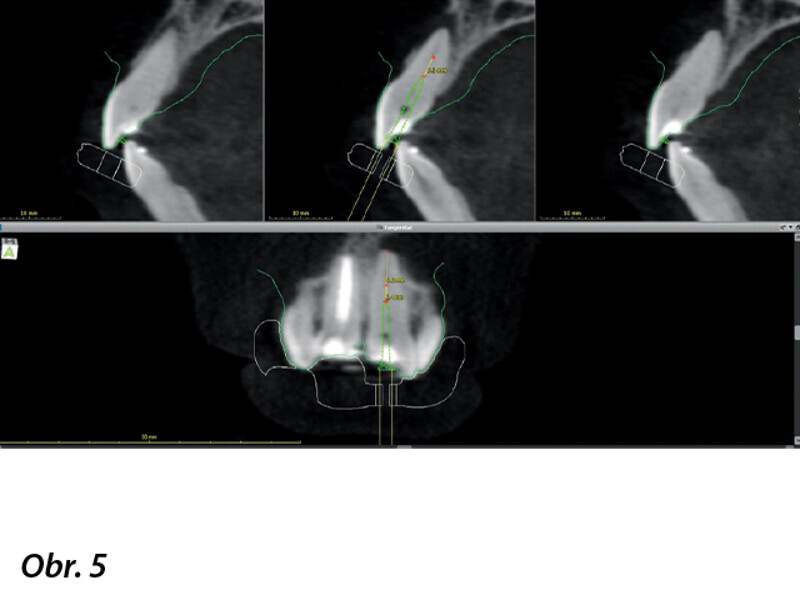

Navigovaný endodontický přístup u kalcifikovaných frontálních zubů: Kazuistika